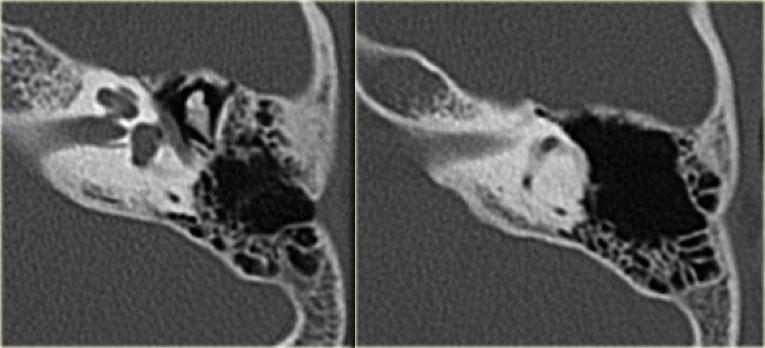

Cholesteatoma: Phụ nữ 20 tuổi với viêm tai tái phát. Mô hạt trên màng nhĩ trái. Khối mô mềm nằm giữa chuỗi xương con và thành nhĩ bên, có hình ảnh bị ăn mòn. Bên phải để so sánh.

Bên trái là hình ảnh của một phụ nữ 20 tuổi với viêm tai tái phát.

Có mô hạt trên màng nhĩ trái.

CT cho thấy một khối mô mềm nằm giữa chuỗi xương con và thành nhĩ bên, có hình ảnh bị ăn mòn.

Điều này ủng hộ chẩn đoán cholesteatoma.

Phụ nữ 20 tuổi với viêm tai tái phát. Mô hạt trên màng nhĩ trái. Khối mô mềm nằm giữa chuỗi xương con và thành nhĩ bên, có hình ảnh bị ăn mòn. Bên phải để so sánh.

Bên trái là các hình ảnh mặt phẳng coronal của cùng bệnh nhân trên.

Lưu ý cholesteatoma đã ăn mòn scutum (mũi tên).